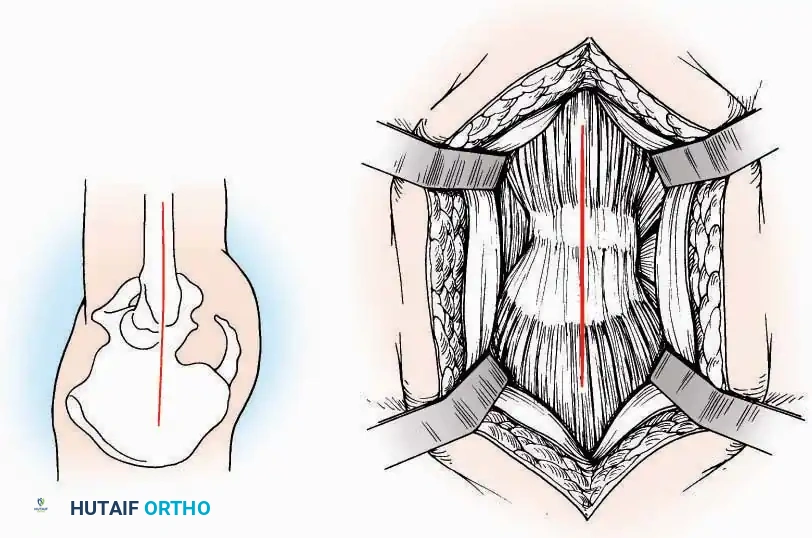

Anterior Approach

Indications: Total ankle arthroplasty (TAA), anterior ankle arthrodesis, and excision of anterior tibial/talar osteophytes (anterior impingement).

Surgical Technique:

* Incision: Make a 10 to 15 cm longitudinal incision over the anterior aspect of the ankle, centered exactly midway between the medial and lateral malleoli.

* Superficial Dissection: Incise the superficial fascia. Identify and protect the superficial peroneal nerve branches laterally and the saphenous nerve medially.

* Internervous Plane: The deep dissection exploits the plane between the Extensor Hallucis Longus (EHL) tendon (innervated by the deep peroneal nerve) and the Extensor Digitorum Longus (EDL) tendons (also innervated by the deep peroneal nerve).

* Neurovascular Bundle: Incise the extensor retinaculum. Carefully identify the anterior tibial artery and the deep peroneal nerve, which typically lie between the EHL and EDL, or directly deep to the EHL. Retract the neurovascular bundle laterally with the EDL, or medially with the EHL, depending on the specific anatomical variant encountered (lateral retraction is most common).

* Capsulotomy: Incise the anterior joint capsule longitudinally. Elevate the capsule subperiosteally from the anterior tibia and the talar neck to expose the entire tibiotalar articulation.